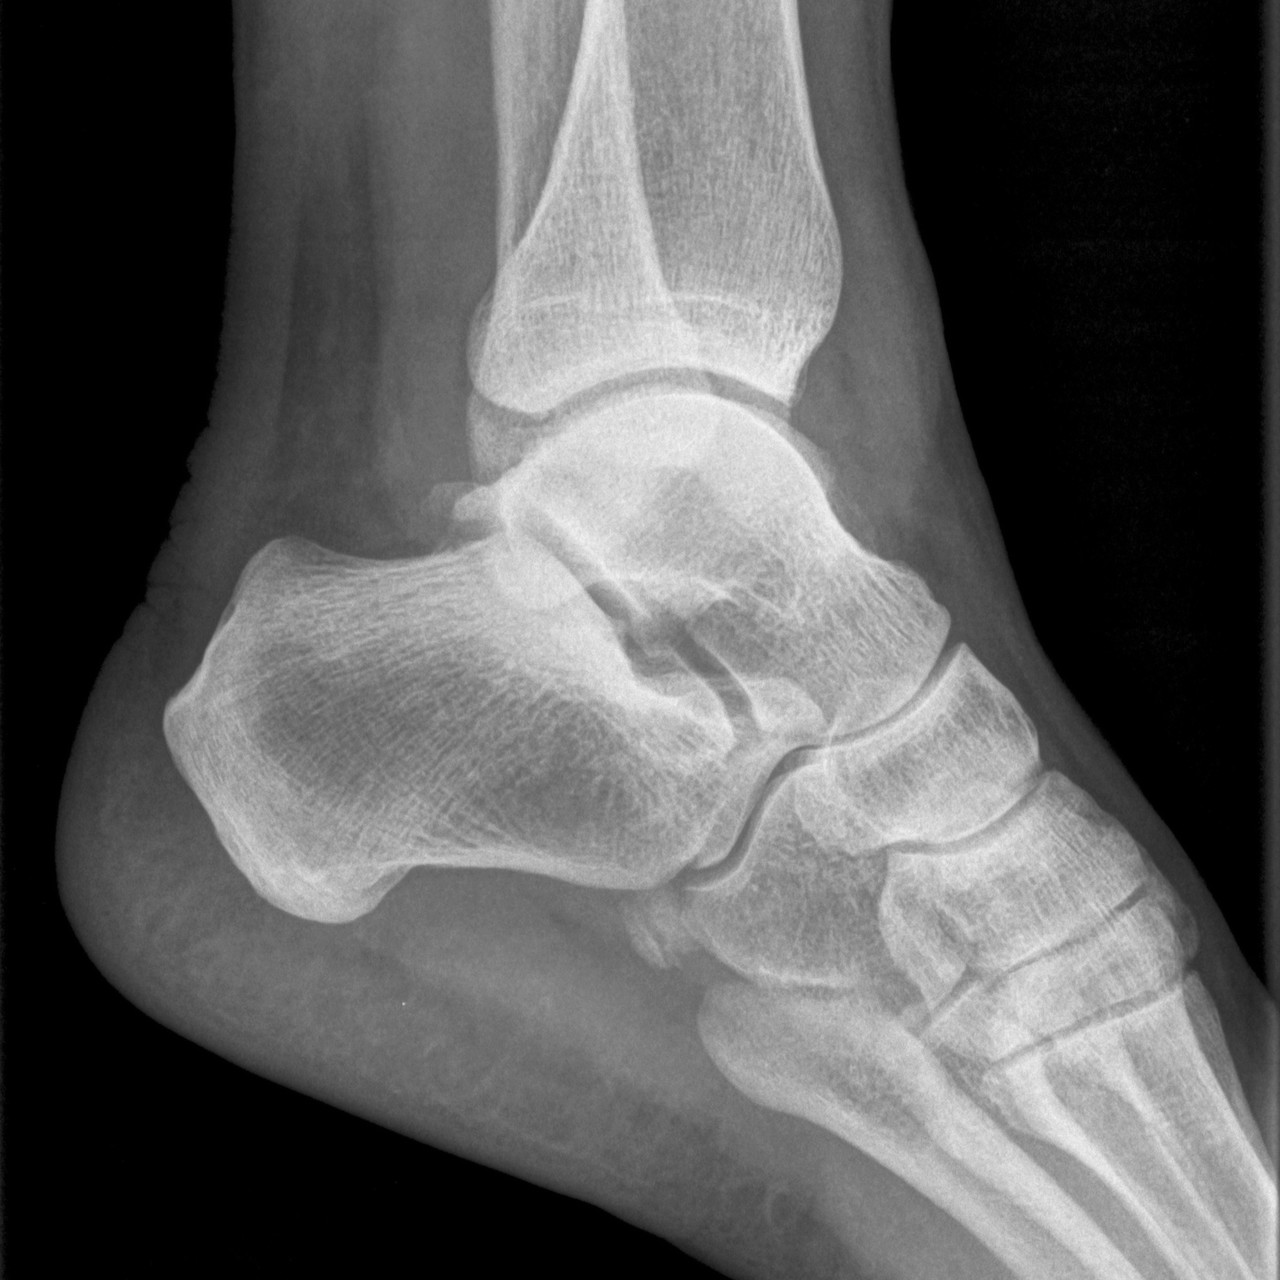

방사선검사로 해부학적 이상 소견 및 발의 정렬, 아치의 높이등을 확인하고 정밀 초음파로 인대 손상여부와 정도를 정확하게 파악하여야 올바른 치료의 방향을 결정할 수 있습니다.

부주상골은 발목뼈 중 주상골 옆에 위치하는 부골(accessory bone)로서 청소년기에 주상골과 하나의 뼈로 유합되는데, 유합하지 못하고 남아있는 것을 말합니다. 부주상골은 인구의 10~20%에서 발견될 만큼 흔합니다.

발목이 바깥쪽으로 꺾이는 외상이나 무리한 운동 후에 발 안쪽의 볼록 튀어나온 부위에 통증이 느껴지고 이것이 반복된다면, 검사 후 부주상골 증후군을 진단할 수 있습니다. 부주상골 증후군은 발목 안정과 아치(arch) 의 높이를 유지하는데 중요한 역할을 하는 후경골건의 부착부위이기 때문에 증상 발생 시 반드시 치료가 필요합니다.